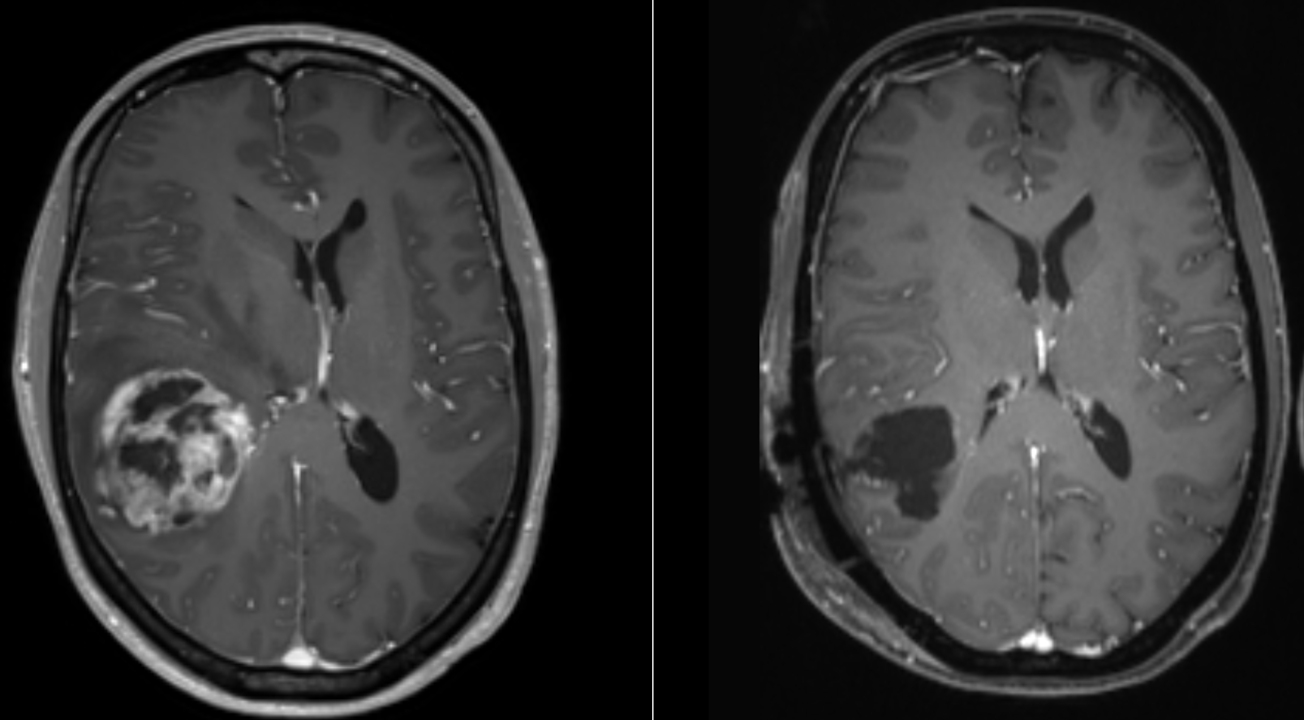

Пухлина гліобластоми до (зліва) та після (справа) видалення. Ars Neurochirurgica / Wikimedia Commons

Порівняно зі звичайним поєднанням імуно- та хімієтерапії, додаткове застосування терапії електричними полями збільшувало шанси на виживання на 70 відсотків. При цьому пацієнти жили без рецидивів у середньому на шість місяців довше за тих, хто лікувався традиційним способом. Ті пацієнти, у яких залишилися великі неоперабельні пухлини, жили на 13 місяців довше за тих, кому гліобластому повністю видалили. Імовірно, це пов’язано з тим, що більша пухлина спричиняє активнішу імунну відповідь. Третю фазу випробувань нової терапії планують провести до 2029 року за участі майже 800 пацієнтів, щоб оцінити її ефективність на різних стадіях хвороби.